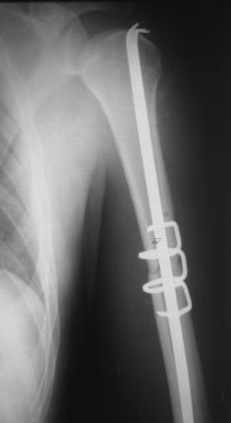

Добрый вечер!

Приложение как пример.

Консервативно он уже лечился до этой операции в течение трёх с половиной месяцев.

А именно такой вариант операции выбран из экономических соображений.

вообще, торчашие в субакромиальное пространство шипы оставляют неизгладимое впечатление. Не думаю, что таким имплантом есть смысл гордиться

Снимок с имплантом из металла с памятью формы получился "sexy", но нарушены все каноны остеосинтеза. Потому что при комбинации двух ущербных систем одновременно повреждается внутри канальное и наружное кровообращение.

Кроме интрамедуллярного остеосинтеза, имеются другие варианты фиксации, наружный фиксатор и например здесь перелом плеча с повреждением нерва леченный открытым методом. Применен задний доступ с инспекцией нерва, межфрагментарная компрессия, фиксация узкой пластиной 4.5 мм.